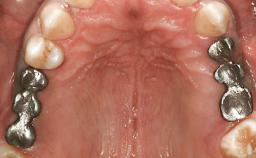

A healthy 26-year-old woman was referred for evaluation and treatment of her failing maxillary right central incisor (tooth 11). She reportedly traumatized the tooth at about age 9 and subsequently had repeated conventional and surgical endodontic procedures and fixed restorations. Despite these procedures, she had recurrent fistulas in the apical mucosa and a mid-facial pocket of 7 mm with suppuration. All other sites on the tooth probed 3 mm without inflammation. She presented with a medium biotype with triangularlyshaped teeth and a moderately high smile line, showing all of her papillas and a few millimeters of marginal gingiva in a full smile.Ceramic veneers were present on teeth 12, 21, and 22, and they were known to be somewhat bulky, eventually requiring replacement. She had a strong desire to avoid additional tooth preparation and would not consider a fixed dental prosthesis to replace tooth 11.